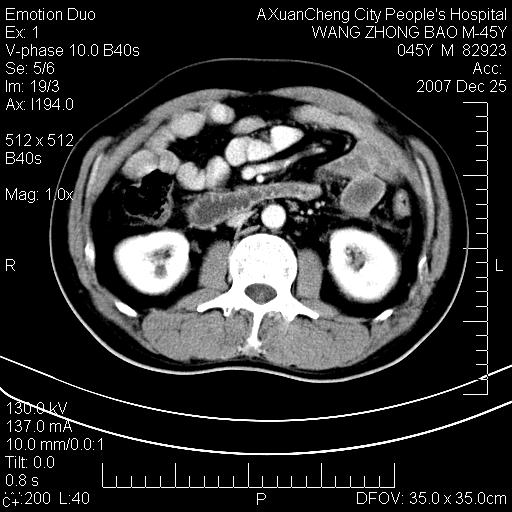

以下是引用卜一在2007-12-25 14:07:00的发言:[br]胰头钩部略增大,与十二指肠壶腹部关系密切,其内明显见软组织密度肿块,明显强化,但肠壁较光滑 柔软。考虑:炎性增生!建议消炎后复查!待除外壶腹部腺癌!

以下是引用qiuleiyu在2007-12-25 18:14:00的发言:[br]胰腺增大,周边渗出改变,肾前筋膜明显增厚,示少量积液.胆囊壁毛糙,周边少许渗出,胆总管壁厚,异常强化,然扩张不明显.结合病程急短;考虑;胆管炎,胆囊炎,胆源性胰腺炎可能大,请结合实验室检查及随访.

以下是引用lisihao在2007-12-25 14:23:00的发言:[br]急性水肿型胰腺炎[br]依据:1、胰腺弥漫性肿大,边缘稍毛糙;[br] 2、双侧肾周筋膜增厚,尤以左侧为甚(重要征象)[br] 3、双侧后胸膜增厚(刺激性炎症);[br] 4、结合病史,查血尿淀粉酶应该可以确诊。